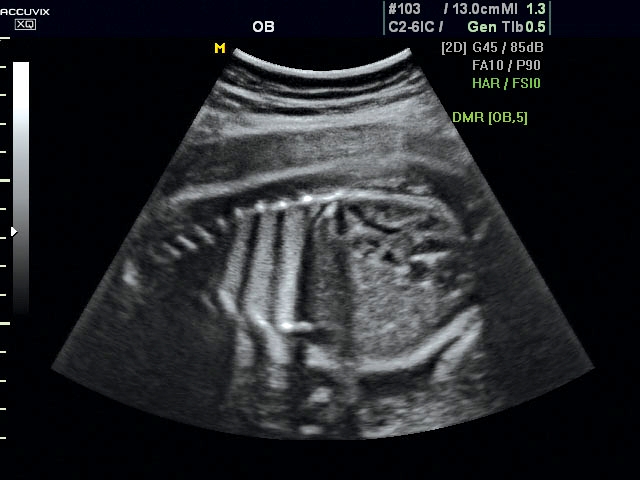

Magzati koponya képe normál 2D módbanMagzati koponya 2D képe bekapcsolt Dynamic MR funkcióvalMagzat törzsének képe normál 2D módbanMagzat törzsének képe bekapcsolt Dynamic MR funkcióvalMagzat felsőajakjának és orrának képeMagzat felsőajakjának és orrának képe bekapcsolt Dynamic MR funkcióval

A DynamicMR alkalmazása az átlagos ultrahang teljesítményt a zaj és szemcsézettség jellegű műtermékek kiszűrése révén a vizuális diagnosztika, a precizitás és a pontosság új szférájába emeli. Figyelje meg a cerebellum, CSP és cisterna magna élstruktúráit, mennyire pontosan definiáltak és a teljes agyi struktúra ábrázolása a Dynamic MR alkalmazásával milyen látványosan javul.